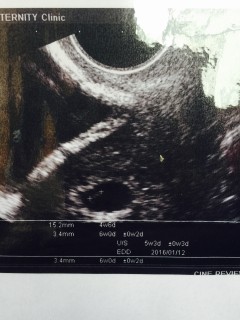

6w5dだったけど大きさで5w3dになりました! 心拍がピコピコ動いてて可愛かったあ(^ω^)

心当たりのある日から数えて5w3dだと思っていたのですが、胎嚢の大きさは14.4mm(4w5dの平均)でした。2週間後に胎芽&心拍確認出来る事を願っています(^^)

写真は5w6dになってますが、基礎体温排卵日などいろいろ考えて5w3dでしょう!と、いわれました! 卵黄嚢も確認でき、ひと安心です。 2週間後に心拍確認にいく予定なので、とてもたのしみです♪